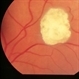

- tuberous sclerosis

- Mulberry lesion.